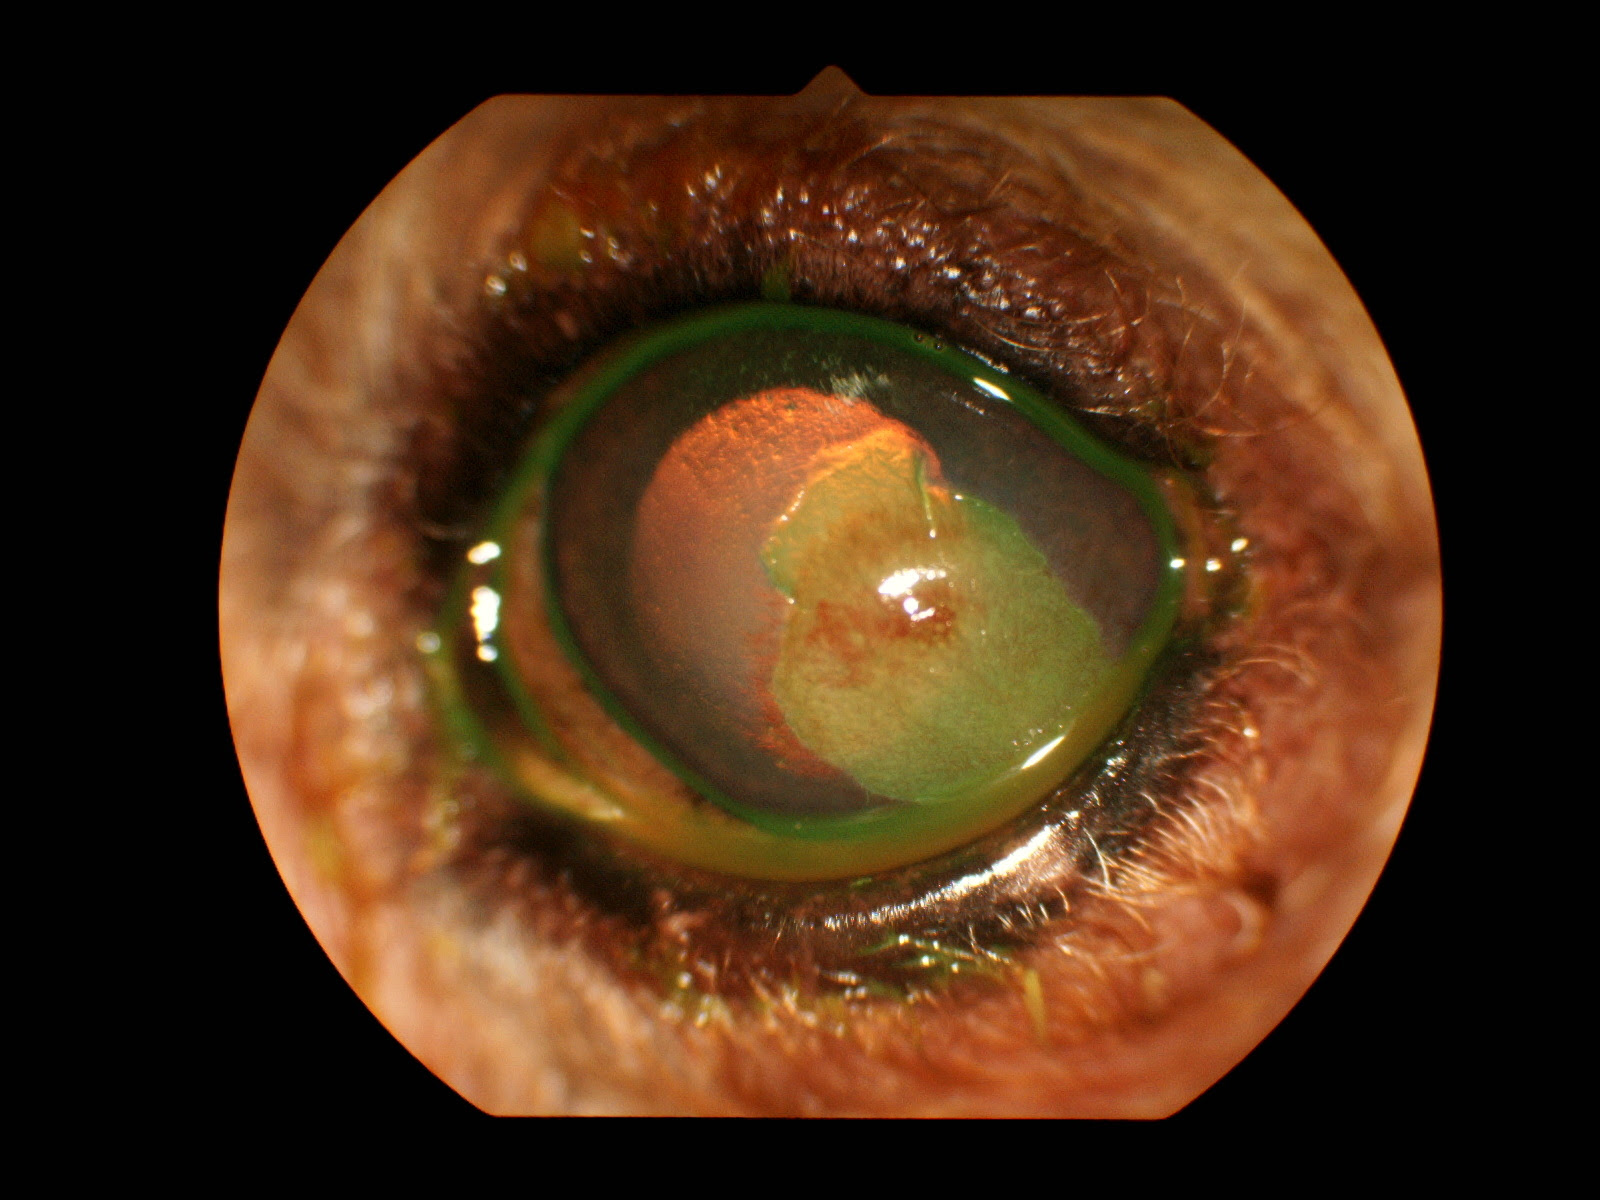

犬角膜炎どのくらいで 治る, 犬の角膜炎獣医師が解説 犬の目に傷が入ると角膜炎を引き起こす場合があります。愛犬の目が充血していたり、目をこするような仕草をしている場合は要注意。 犬はkcsを持つ子が多く、角膜潰瘍に発展しやすいです。 他にも、感染や目の奇形によって角膜に傷ができやすくなることがあります。 角膜潰瘍を治療するには? 角膜潰瘍の治療は点眼薬がメインとなります。角膜炎とは、何らかの原因によりこの角膜に炎症が起きている状態のことです。 角膜炎の主な原因としては慢性的な刺激や自己免疫異常、感染や外傷などが挙げられます。 犬の角膜炎の症状 角膜炎の症状は以下のようなものがあります。 <犬の角膜炎>

犬 角膜炎 どのくらい で 治る 柴犬は少ないですね。 角膜潰瘍とは、最初の図のように眼の表面にあるカプセルの部分に傷がついた時の病名です。 図のように角膜は1層ではないので、どこまで傷がついたかという事で治療が異なります。 上皮欠損程度は 犬の角膜潰瘍の症状と治療の記録目薬で完治するまでの期間など 18年4月19日 パピヨンのチヨ (16歳)、半年ほど前に黒目に白い点を発見。 診察の結果、角膜潰瘍か角膜ジスロトフィーかということで、目薬による治療を行ったところ改善が見られた

治りが悪い 眼がショボショボしている 角膜潰瘍 神奈川県川崎市麻生区の動物病院 ハルどうぶつ病院 犬 猫のワクチン接種 健康診断 椎間板ヘルニア手術 眼の病気 内視鏡手術